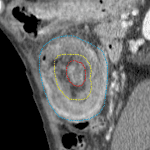

- Colo-colonic intussusception at the splenic flexure measuring 10 cm in length with a 3.5 x 2.5 cm mass at the distal margin of the intussusceptum

- Edematous appearance of the intussusceptum

- Malignant colo-colonic intussusception

Colo-colonic intussusception at the splenic flexure measuring 10 cm in length with edema and possible early ischemic changes of the intussusceptum. Mass at the distal margin of the intussusceptum is concerning for a neoplastic lead point. Recommend surgical evaluation.